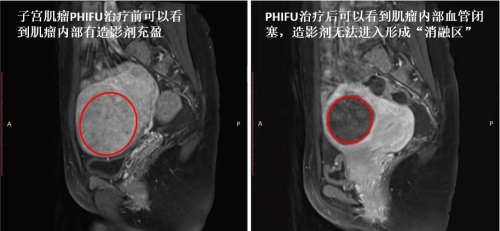

治疗后一个月,复查发现J女士的子宫肌瘤消融率100%(见下图红圈标注区),六个月后子宫肌瘤缩小率达50%以上。腹部没有伤口,也未发现明显的毒副作用,在PHIFU的精准定位下,病灶部位肌瘤消融,而周围正常子宫肌层和子宫内膜未受损伤,子宫肌瘤得到有效减小,月经也逐渐恢复正常。